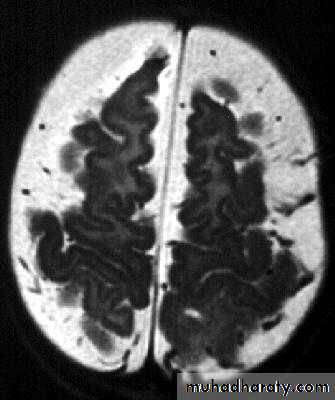

Brain Abscess MRI

Neurosurgery